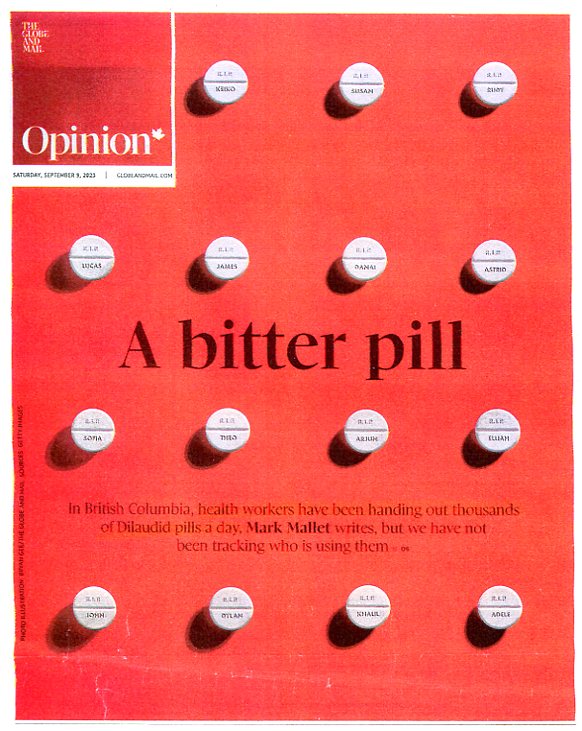

(gov't giving away hydromorphone dillies like candy)

ORWELLIAN WAR BY DRUGS